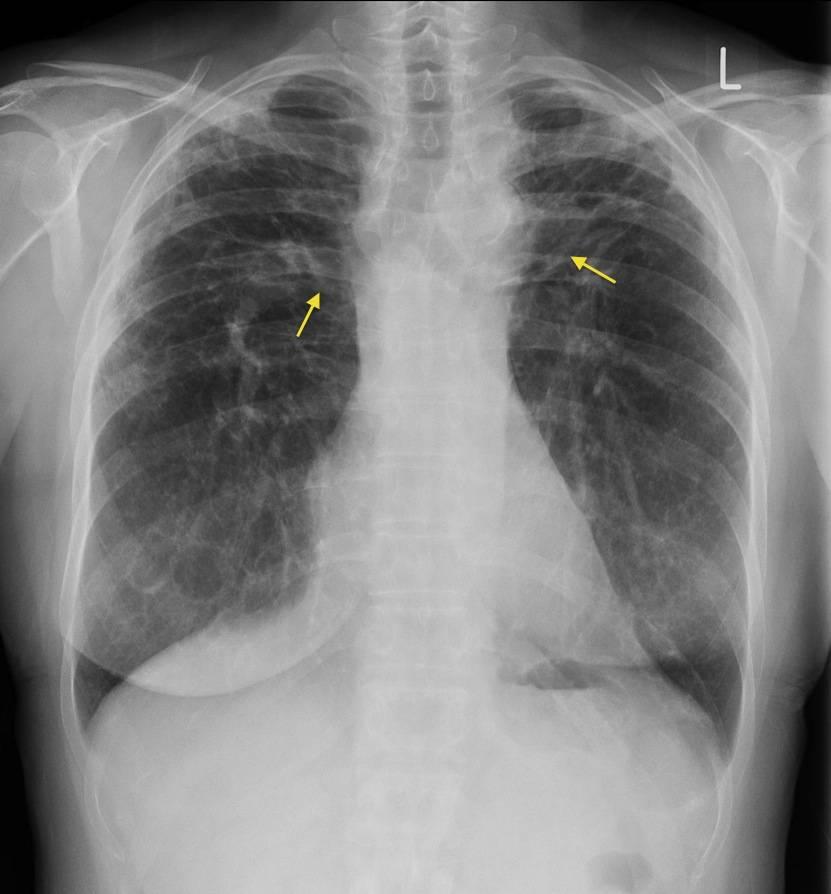

Evaluarea inițială realizată de echipa medicală pornește de la anamneză detaliată și examen clinic, urmând investigații imagistice care pot ajuta la identificarea pattern‑urilor sugestive ale bolii, precum radiografia toracică și tomografia computerizată (CT) toracică. Aceste investigații imagistice pot contribui la evidențierea adenopatiei mediastinale și a modificărilor pulmonare tipice, dar nu sunt întotdeauna suficiente pentru confirmare fără alte date clinice.

Teste funcționale respiratorii, cum ar fi spirometria și măsurarea difuziunii, pot susține evaluarea gravității afectării pulmonare, iar proceduri invazive precum bronhoscopia cu lavaj bronhoalveolar și diverse tehnici de biopsie (transbronșică, transbronșică ghidată sau chirurgicală) pot ajuta la obținerea materialului pentru examen histologic când este necesar. Rezultatele histologice și clinice sunt interpretate împreună de echipă pentru a evita concluzii izolate.